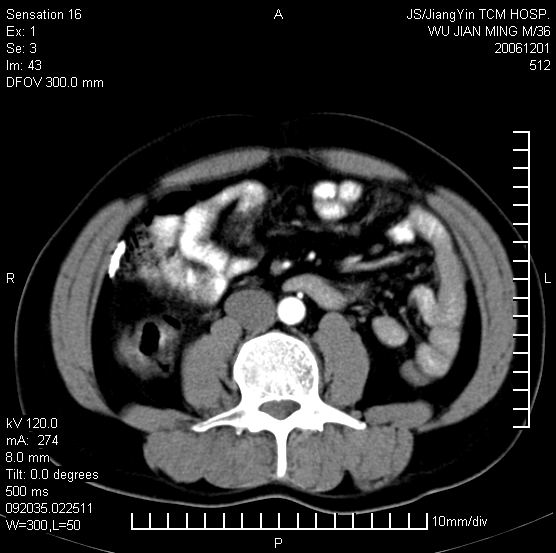

以下是引用dyqct在2006-12-1 21:17:00的发言:[br]左心缘旁及后肋膈窦区见巨大椭圆形混杂密度肿块,周围见大小不等斑片状钙化,内部无强化,周围包膜轻度强化,心脏明显受压变形,即明显占位效应,肿块广基与心包、膈相连。肝、脾内、肝门见多数小结节状钙化影。[br]考虑:1、左心缘旁及后肋膈窦区慢性包裹性胸膜炎(结核性);[br] 2、肝、脾及肝门淋巴结核已钙化。[br]

以下是引用zrs在2006-12-2 17:28:00的发言:[br]肺内、肝脾内虽有钙化,但不支持结核性胸胸膜炎包裹,而支持寄生虫感染![br][br]

以下是引用zyx168在2006-12-2 10:10:00的发言:[br][br]肝脾肺内多发钙化灶